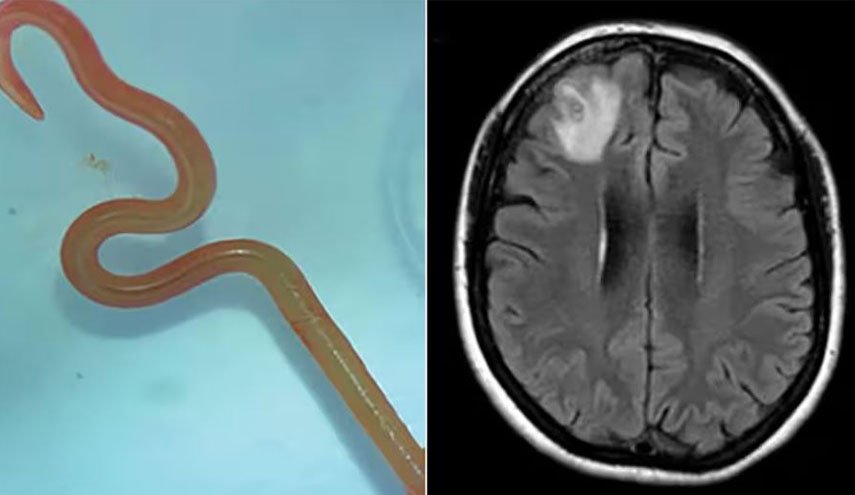

وأضافت: "الأكثر شيوعًا دودة شريط لحم الخنزير، تينيا سوليوم (أو داء الكيسات العصبية)".

والطريقة الأساسية لانتقال هذه الديدان لأدمغتنا هي عن طريق الخنزير لا سيما عندما يستهلك لحم الخنزير النيء أو غير المطبوخ جيدا ما يسمح لهذه الدودة الشريطية بالدخول لأجسامنا.

بحسب بيتسي فإن هذه الدودة لا يمكنها الانتقال إلى الدماغ لكن يرقاتها يمكنها ذلك، حيث تضع الدودة يرقاتها بمجرد دخولها للأمعاء مستخدمة أجسامنا كوسيط، وإذا لم يتم طرد البيض من أجسامنا من خلال البراز، فقد تنمو إلى يرقات.

يمكن لهذه اليرقات أن تنتقل إلى أعضاء أخرى من خلال مجرى الدم، قد تنتقل هذه الديدان الشريطية أيضا من إنسان إلى آخر إذا كان لدى الشخص عادات غير صحية مثل عدم غسل يديه جيدًا بعد استراحة الحمام.